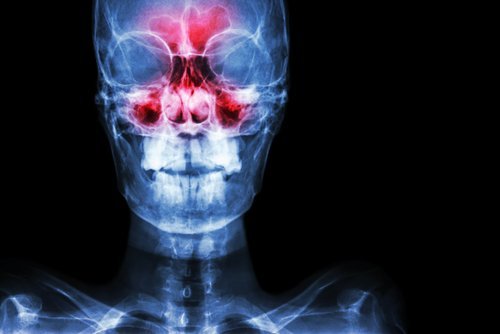

La sinusite è una malattia dei seni paranasali, piccoli spazi vuoti in cui passa l’aria che circola tra le ossa del naso. Si dividono in tre gruppi: seni frontali, seni etmoidali e seni mascellari.

In condizioni normali, l’aria si sposta senza problemi attraverso queste cavità. Al contrario, quando i seni paranasali si infiammano, sorgono difficoltà respiratorie e altri fastidi come un dolore che a volte può essere molto intenso.

Nella maggior parte dei casi si formula una diagnosi di sinusite partendo da un’ispezione delle fosse nasali. Il medico proietta una luce sulla zona in cerca di polipi o segni di infiammazione.

È ugualmente frequente applicare pressione sull’area per verificare se sussiste il dolore. Il palesarsi del dolore suggerisce la presenza di sinusite.

Per realizzare una diagnosi certa, in generale si prescrivono uno o vari dei seguenti esami clinici: rinoscopia, tomografia computerizzata o risonanza magnetica.

Le radiografie difficilmente ottengono un risultato affidabile.